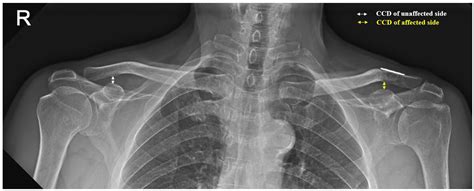

• AC Joint Separation: This occurs when the ligaments supporting the AC joint are torn, often due to a fall or direct impact. It is graded on a scale from I to VI, with higher grades indicating more severe injuries.

• Joint Space: The space between the clavicle and scapula should be uniform. Any narrowing or widening can indicate injury or degeneration.

• Bone Alignment: The bones should be properly aligned. Any displacement or misalignment can suggest a fracture or dislocation.

• Bone Density: Changes in bone density can indicate conditions like osteoporosis or bone tumors.